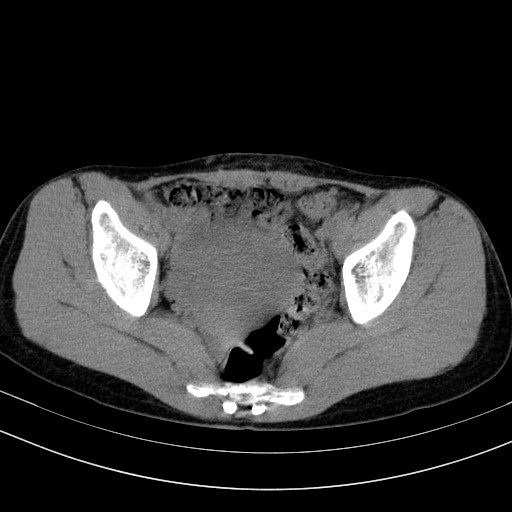

以下是引用卜一在2009-4-7 5:08:00的发言:[br]宫颈癌可能。支持!

以下是引用随光逐影在2009-4-7 8:17:00的发言:[br]考虑宫颈占位性病变(宫颈癌?);建议行进一步检查。

以下是引用jiangjing在2009-4-7 16:46:00的发言:[br]宫颈增大,结构不清,右侧附件区可疑囊样占位,建议增强及mri 检查